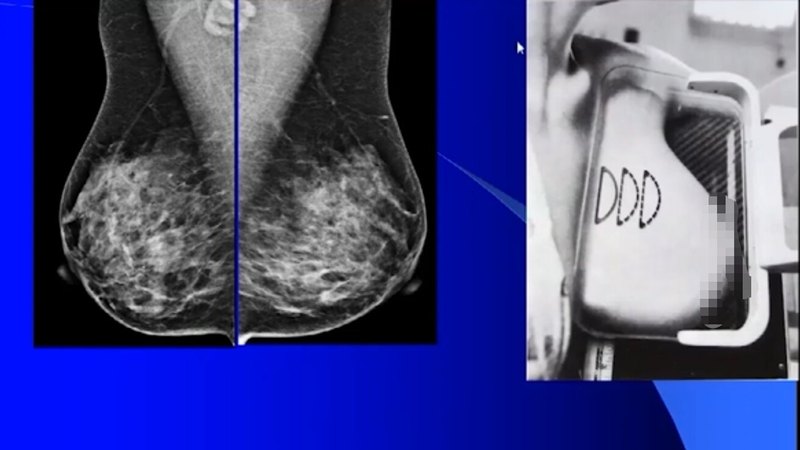

乳腺疾病影像學(xué)檢查,一個(gè)重要的目的是診斷惡性腫瘤。乳腺癌是一種讓女性非常擔(dān)心、恐懼的惡性腫瘤,在女性發(fā)病率為第一位。乳腺癌改善預(yù)后,就要“早發(fā)現(xiàn),早診斷、早治療。目前檢查方法主要有三種,①X線檢查,鉬靶軟X線攝影(有斷層檢查DBT和對(duì)比增強(qiáng)CEM技術(shù)),②B超檢查,③磁共振(MRI)檢查。鉬靶和B超兩者結(jié)合是當(dāng)前國際上廣泛采用的檢查方法,并被認(rèn)為是最佳的黃金組合。然而,磁共振成像優(yōu)勢(軟組織分辨率好,無輻射),成為重要的補(bǔ)充檢查方法。各種影像檢查,醫(yī)生力求做到定位、定量、定性、定期,但都所長和不足。X線檢查由于病變與正常組織有密度差,從而檢出病變。依據(jù)病變的形態(tài)學(xué)表現(xiàn)進(jìn)一步做出診斷和鑒別診斷。超聲:依據(jù)灰階成像,做出形態(tài)學(xué)診斷,不止能觀察病變血流(CDFI),此外,還有容積成像,彈性成像技術(shù),造影技術(shù)。磁共振檢查成像參數(shù)多,可行平掃(不打增強(qiáng)藥物)、動(dòng)態(tài)增強(qiáng)(打增強(qiáng)劑進(jìn)一步觀察病變)、DWI(彌散成像技術(shù))、MRS(波譜成像)。鉬靶檢查一般照內(nèi)列斜位和頭尾位片,有時(shí)為進(jìn)一步顯示病變而行加壓照片。內(nèi)外斜位(MLO)所暴露出的乳腺組織最多,對(duì)一些深位病變顯露較好。標(biāo)準(zhǔn)斜位照片:胸大肌充分顯示,且延伸至或低于后乳頭線;可見所有纖維腺體組織后的脂肪;深部和表面乳房組織分離充分;乳房下皺褶打開;照片無明顯運(yùn)動(dòng)偽影。頭尾位(CC位)照片:內(nèi)側(cè)乳房組織充分顯示,乳頭位于影像中心;在乳房后部可見部分胸大?。s20%病例可見,膠片邊緣)。超聲檢查要規(guī)范,縱掃、橫掃、放射性掃和反放射性掃查等幾種。常規(guī)二維灰階圖像、血流圖像,而彈性成像技術(shù)區(qū)別不同質(zhì)地病變,如脂肪瘤比較軟,做增強(qiáng)看強(qiáng)化范圍,高強(qiáng)化、低強(qiáng)化和曲線,總體判斷良惡性。磁共振檢查為俯臥位,雙側(cè)乳腺同時(shí)成像,需注射對(duì)比劑。一般檢查時(shí)間約30分鐘。各種影像檢查都存在診斷局限性,直接影響診斷準(zhǔn)確性??陀^存在,由成像特點(diǎn)決定。其中X線對(duì)致密型乳腺中的非鈣化病變檢出率較低。對(duì)病變內(nèi)部組織結(jié)構(gòu)觀察存在局限性。對(duì)于小乳房投照困難。而對(duì)鈣化型乳腺癌的顯示明顯優(yōu)于其他方法。X線片檢查技術(shù)標(biāo)準(zhǔn)化,可集體讀片會(huì)診。B超對(duì)致密型乳腺和病變內(nèi)部結(jié)構(gòu)的顯示明顯優(yōu)于X線檢查。診斷參數(shù)較多。對(duì)于小乳房檢查便利,受射線輻射。B超的局限性:對(duì)微小鈣化檢出率敏感性不如X線。診斷準(zhǔn)確性很大程度取決于所檢查醫(yī)生的個(gè)人經(jīng)驗(yàn)、病變本身特點(diǎn)和乳腺組織構(gòu)成情況。